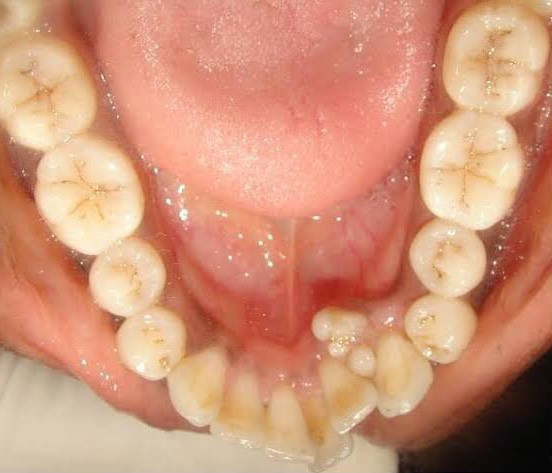

When you hear the word "tumor," there's a good chance you think of cancer. Fortunately, with an odontoma, that's not the case. While an odontoma is a tumor, it's a benign one and not uncommon. That alone is great news! However, odontomas usually require surgical removal. They're made up of dental tissue that resembles abnormal teeth or calcified mass that invade the jaw around your teeth and could affect how your teeth develop. Fortunately, treatment is pretty straightforward and the road to a tumor-free life is one frequently traveled.

There are 2 main types of odontomas:

Compound:

Consisting of many, tiny tooth-like bits

Usually found in the lower jaw

Most often occurs during your teenage years

It affects men and women equally